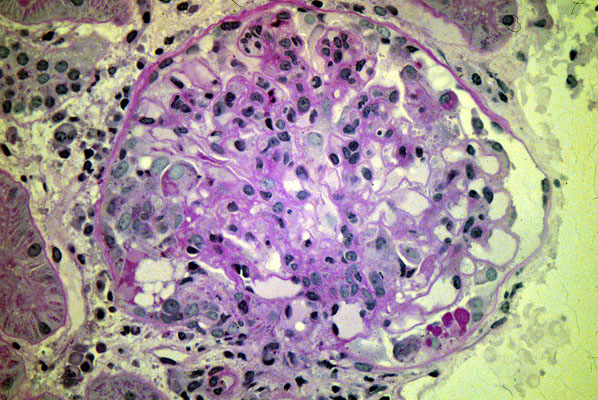

Lupus nephritis, Class III

Focal mesangioproliferative

glomerulonephritis

(Lupus class IV, diffuse

lupus nephritis

, will look the same when examining just one

glomerulus

).